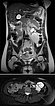

Coronal and axial T2-weighted HASTE sequences without contrast 8 weeks after delivery. Postpartum, there is again a marked reduction in the size of the venous malformation.

The venous malformation showed a clear size decrease 8 weeks after delivery, so that minimally invasive treatment by sclerotherapy is currently not necessary for the nursing mother. The large venous malformation was asymptomatic at this time.